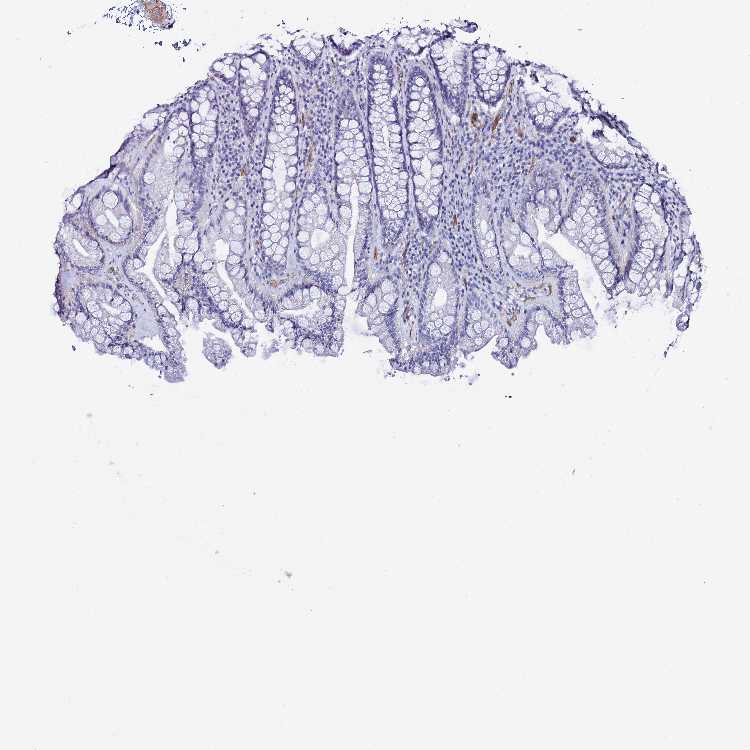

DEFB104A